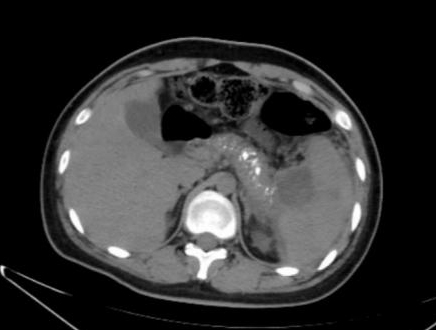

患者男,17岁,主因“反复腹痛2年,加重伴发热2 d”来诊。患者于2019年起常于进食后出现腹部不适、纳差、腹痛,服用“胃药”对症处理后可好转,此后反复发作,频繁时半月发作一次。2020年9月下旬患者进食油腻食物后出现脐周及左中腹部胀痛,无恶心、呕吐,当地医院腹部CT提示:慢性胰腺炎急性发作,经对症治疗后2~3 d好转,此后每月有类似症状发作一次。2021年1月18日到本院基本外科门诊查胰腺功能,血清淀粉酶73 U/L,脂质624 U/L; 血钙正常; 血脂4项正常; 检查肿瘤指标,CA-125: 46.9 U/mL(升高),余为阴性; 甲状旁腺素正常; 血清IgG四项:IgG3 154 mg/L(降低),IgG4 1 600 mg/L(升高)。腹盆CT示胰腺多发钙化,胰尾囊肿形成(图 1)。1月22日患者进食汤面后出现腹部不适、纳差、乏力。1月24日晨起后出现腹部剧烈疼痛,伴发热,最高37.6℃,无恶心呕吐,无腹泻,于本院急诊就诊查血象正常,超敏C反应蛋白142.15 mg/L,胰腺功能:血清淀粉酶130 U/L, 脂质1 127 U/L。行腹盆CT检查示:胰腺饱满伴多发钙化,胰周脂肪密度稍增高,可见多发索条影,符合慢性胰腺炎改变(图 2)。予厄他培南抗感染及抑酸、补液等支持治疗后症状略好转,于1月26日收入本院急诊留观继续治疗。既往史:早产儿(32周),右桡骨小头骨纤维瘤术后,过敏性哮喘。个人史:否认饮酒史。家族史:父母体健,无其他特殊情况。

图 1 患者2021-01-19腹部CT